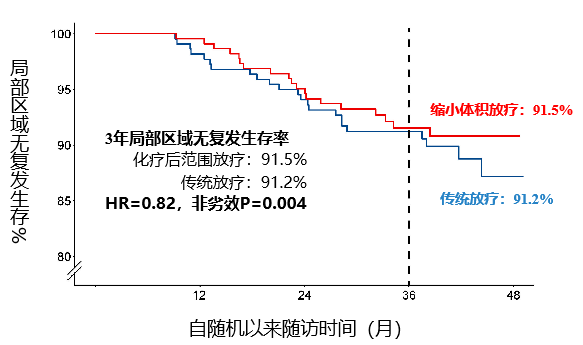

研究结果表明,与化疗前肿瘤范围放疗组相比,化疗后治疗范围放疗组局部区域无复发生存率实现非劣效目标(非劣效P=0.004)、总生存率也没有无差异(P=0.067)。

3年局部区域无复发生存率:91.5% vs. 91.2%